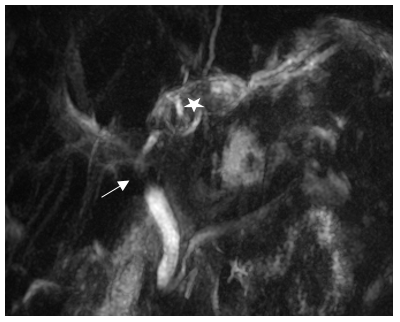

Ultrasonography showed a suspicious left hepatic duct stone with a dilated common bile duct and left biliary radicals. A contrast enhanced computed tomography scan of the abdomen and pelvis demonstrated an atrophic left lobe with multiple hypodense liver lesions suggestive of stones, particularly in segments II and III, with the largest measuring approximately 4 cm, likely representing a liver abscess with a cluster sign due to recurrent pyogenic cholangitis (Figure 1). MRCP confirmed evidence of a dilated left intrahepatic bile duct with multiple stones, associated with edema of the left liver lobe, findings consistent of oriental cholangiohepatitis. The common bile duct was dilated with multiple small stones (Figure 2). Patient underwent ERCP using Spyglass that failed to opacify the Left IHBR by to complete obstruction of the LHD due to giant stone. CBD clearance was performed with plastic stent insertion (Figure 3).

Figure 3. MRCP MIP image showing the large stones (star) in the peripheral duct of segment II; there is also narrowing / stricture of the common hepatic duct (arrow).